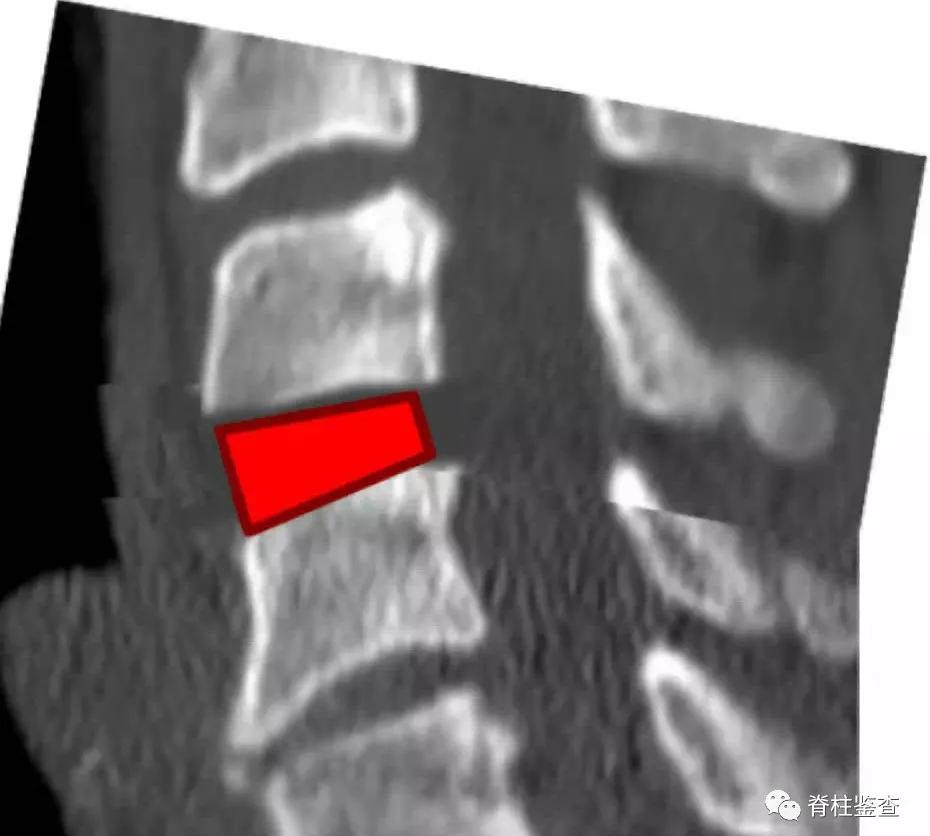

所以,医生一般给颈椎病患者(或多或少都有生理曲度问题)做前路手术时, 红色区域cage都要前凸后凹 ,就是为了保持生理曲度。